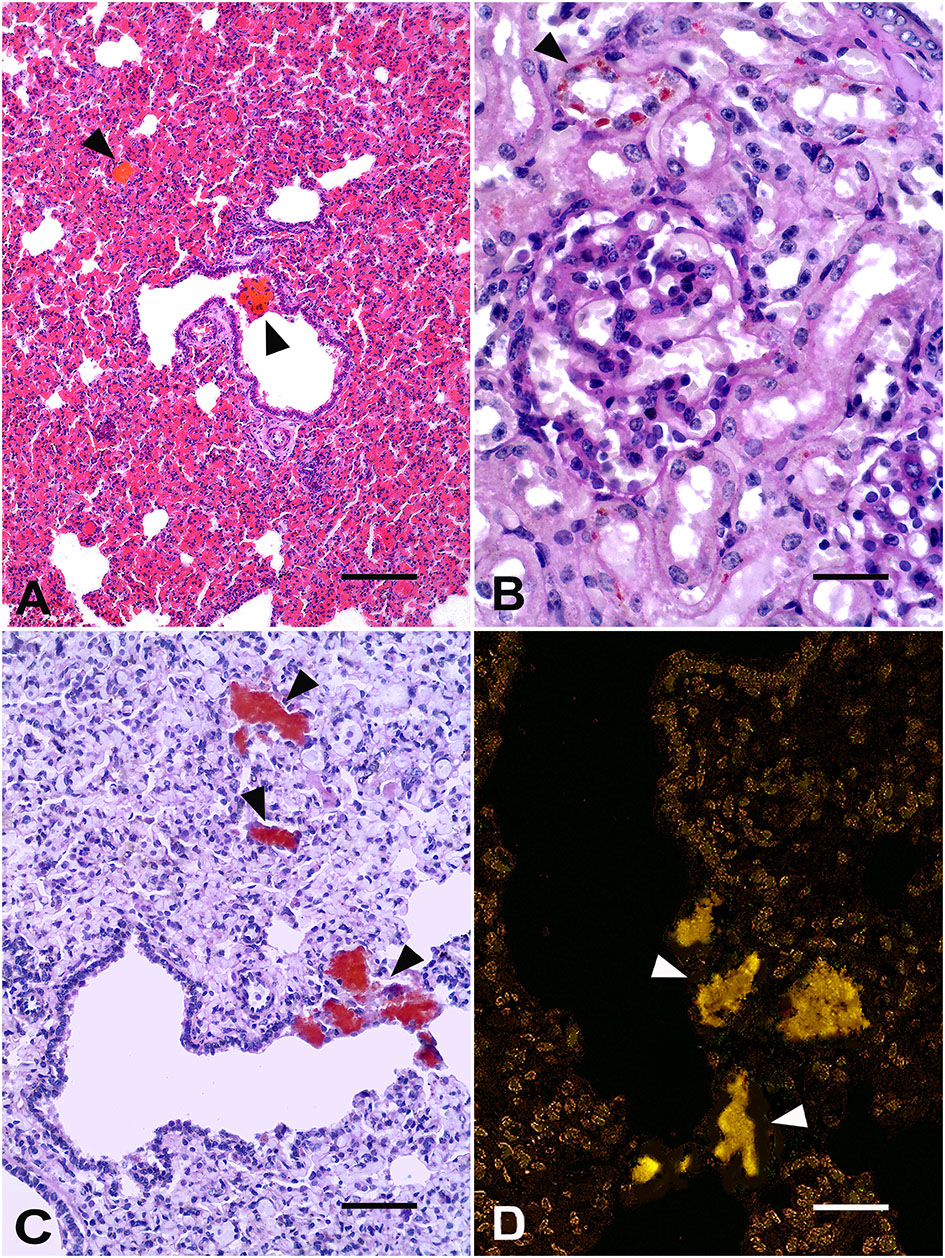

Gir calf. (A) Lung: deposits of brown-orange porphyrin pigments (arrowheads) in the bronchiolar lumen. H&E, Bar = 50 μm. (B) Kidney: orange-brown granules of porphyrin within the cytoplasm of renal tubule epithelial cells (arrowhead). Periodic acid-Schiff (PAS) stain, Bar = 25 μm. (C) Lung: deposits of porphyrin in the alveoli and pulmonary septa and interstitium (arrowheads). PAS stain, Bar = 25 μm. (D) Lung: orange-yellow spontaneous fluorescence of porphyrin aggregates (arrowheads). Unstained lung, fluorescence microscopy, Bar = 25μm.

The staining of periodic acid-Schiff (PAS) leads to strong staining of porphyrin deposits in the epithelial cells of renal tubules (Figure 2B) and in the pulmonary alveoli, epithelium, and bronchiolar lumen (Figure 2C). Porphyrin deposits showed negative Perls Prussian blue staining. Additionally, porphyrin deposits showed an orange-yellow spontaneous fluorescence in the unstained lung (Figure 2D) and kidney sections under a fluorescence microscope (spectral transmission: 550–610 nm) (2, 16). Aspiration bronchopneumonia with moderate, multifocal neutrophilic infiltrates associated with an amphophilic fluid material inside the alveoli was also detected. Thus, a neonate calf with pink teeth, a fluorescent bright pink-red color of bone marrow and articular surfaces under the exposure of UV light, and the microscopic evidence of porphyrin deposits in different tissues enabled the diagnosis of a probable case of CEP (2, 4, 17, 18).

Histological findings detected in the Gir calf are not usually described or assessed in the affected cattle and can be typically unremarkable or unrelated to porphyrin deposition (7, 24). Porphyrin aggregates within renal tubular epithelial cells and lungs have previously been reported in other cases in cattle (4) and were similar to those detected in humans and cats with CEP, including the orange-yellow spontaneous autofluorescence under UV light microscopy (16, 25). Porphyrin pigment deposition may be frequent in many human tissues, such as the lungs, heart, adrenal glands, kidneys, liver, spleen, bone marrow, and choroid plexus (25). Mild porphyrin deposition in renal tubular epithelial cells did not cause renal function impairment or damage in the calf, in contrast to the severe porphyrin-associated renal failure reported in cats (16). Serum, urine, and fecal porphyrin levels were not evaluated in the Gir calf; however, they were believed to be low because anemia, hemolysis, and urine color changes were not detected. Hemolytic anemias are usually associated with high serum levels of porphyrin (25). Considering that the staining of PAS porphyrin pigment is not specific, the absence of staining of the iron pigment in the suspected porphyrin aggregates in the tissues (negative Perls Prussian blue staining) strengthens the diagnosis of porphyrin pigment deposition (16, 25) in the calf. Despite the laboratory test limitations of our study, discoloration of the teeth, periosteum, and bone marrow of long bones and bright pink-red fluorescence of bone marrow and articular surfaces under UV light exposure, in addition to microscopic findings, characterized the first likely case of CEP in a Zebu calf.